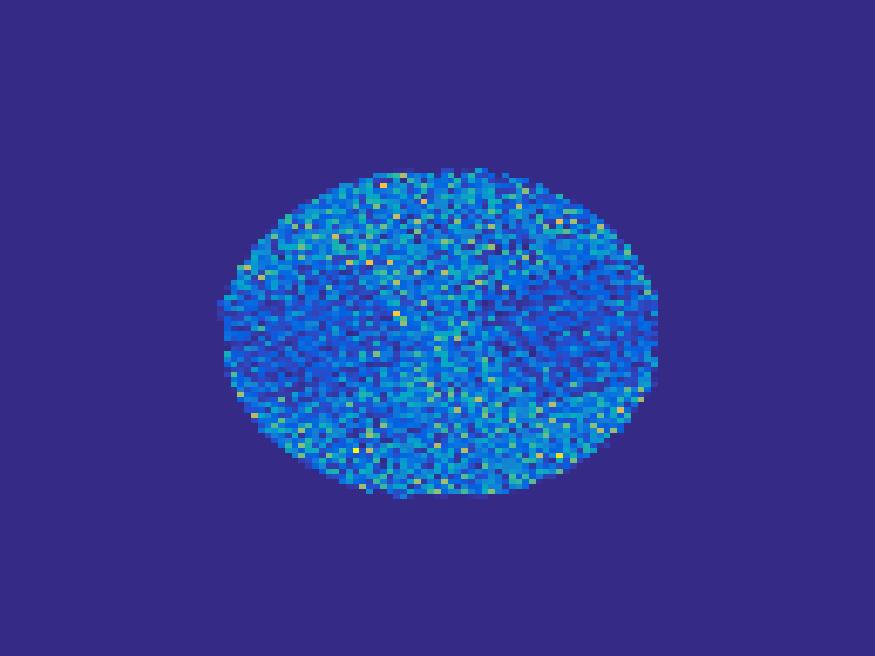

We also perform Monte carlo simulation on the more complex images: the rat’s abdomen phantom. By setting , the sinogram image is shown in Figure 17.

The images reconstructed can be found in Figure 18 for . Figure 19 illustrates the comparison of the true TACs and those reconstructed by the proposed method. We can see that the proposed method is robust to reconstruct most of the structures present in the images.